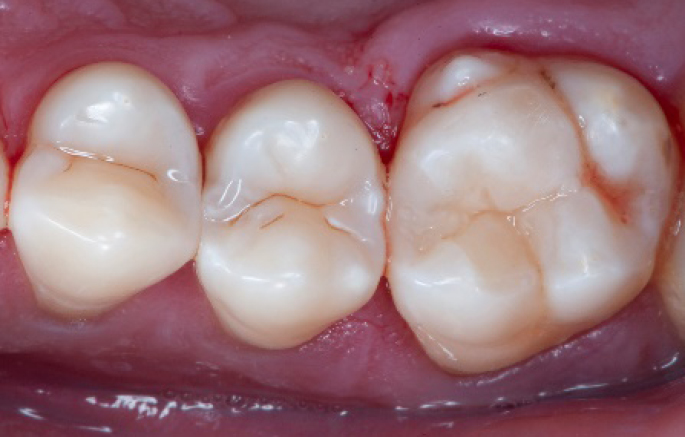

Initial situation of the patient

The patient came for a routine control appointment. She didn‘t report any symptoms but some bleeding during brushing.

Initial situation: an old class I composite restoration on 1.6. New caries on the mesial wall. Presence of plaque and inflammation.

• On the x-ray examination, a mesial translucency (initial caries) was found on tooth 1.6.

• The tooth presented an old class I composite restoration.

• Marginal inflammation and plaque were present.

• No symptoms were referred by the patient.